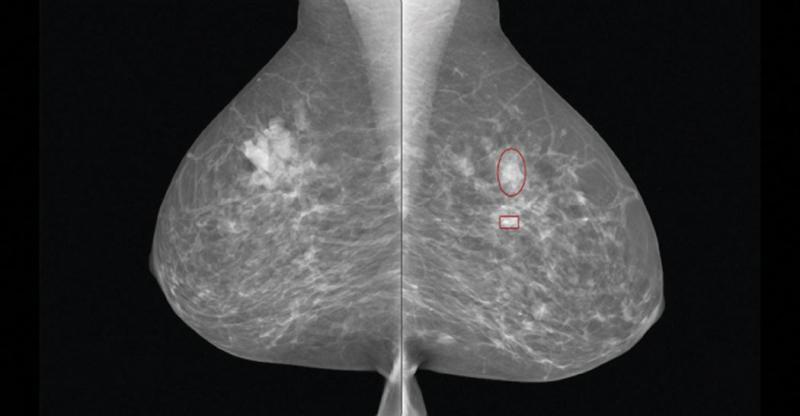

The FDA also approved Siemens’ 3-D mammography imaging system with breast tomosynthesis option, marking its tomo debut in the U.S. market. Siemens’ Mammomat Inspiration with Tomosynthesis Option is a breast tomosynthesis add-on option for Siemens Mammomat Inspiration digital mammography platform. Its breast tomosynthesis algorithm reconstructs multiple 2-D images of the breast into an approximation of a 3-D image to enable detection of tumors that are hidden by overlapping breast tissue. This helps to provide a more accurate diagnosis than standard 2-D digital mammography alone and helps to reduce the number of false-positive findings. In tomosynthesis mode, the X-ray tube of the Mammomat Inspiration rotates in a circular motion around the breast to acquire an image every two degrees while moving through an angular range of 50 degrees. The resulting 25 projections are reconstructed as

three-dimensional digital breast tomosynthesis (DBT) images.